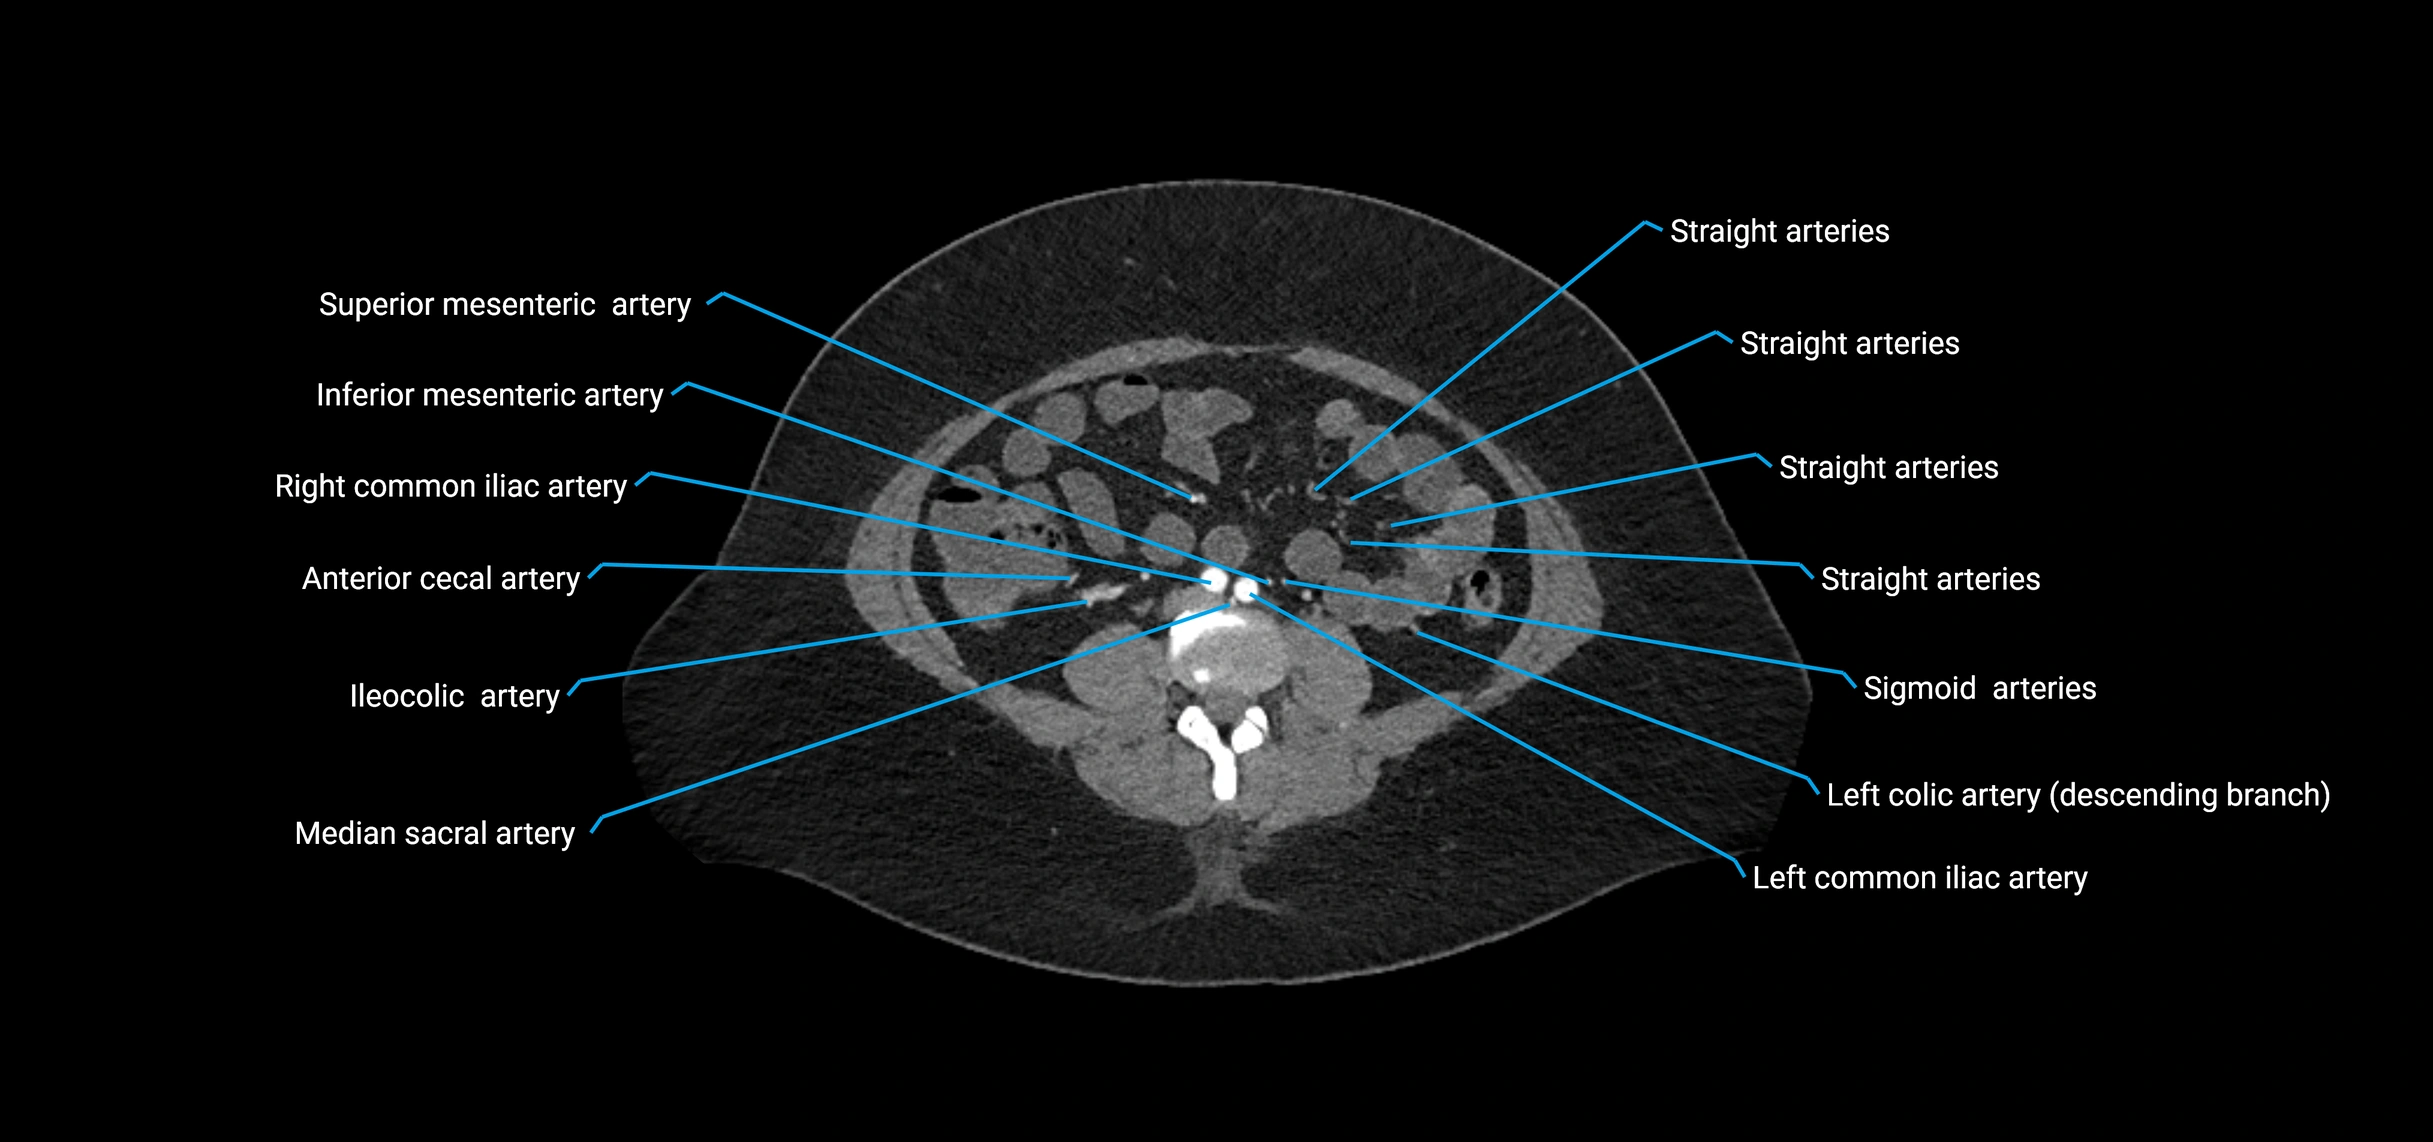

Contrast-enhanced CT (CTA):

• Gold standard for abdominal aortic imaging

• Provides excellent detail of lumen, wall, aneurysm, thrombus, and branch vessels

• Multiplanar and 3D reconstructions help in aneurysm measurement, stent graft planning, and dissection evaluation

• Detects acute rupture, traumatic injury, or occlusion with high sensitivity